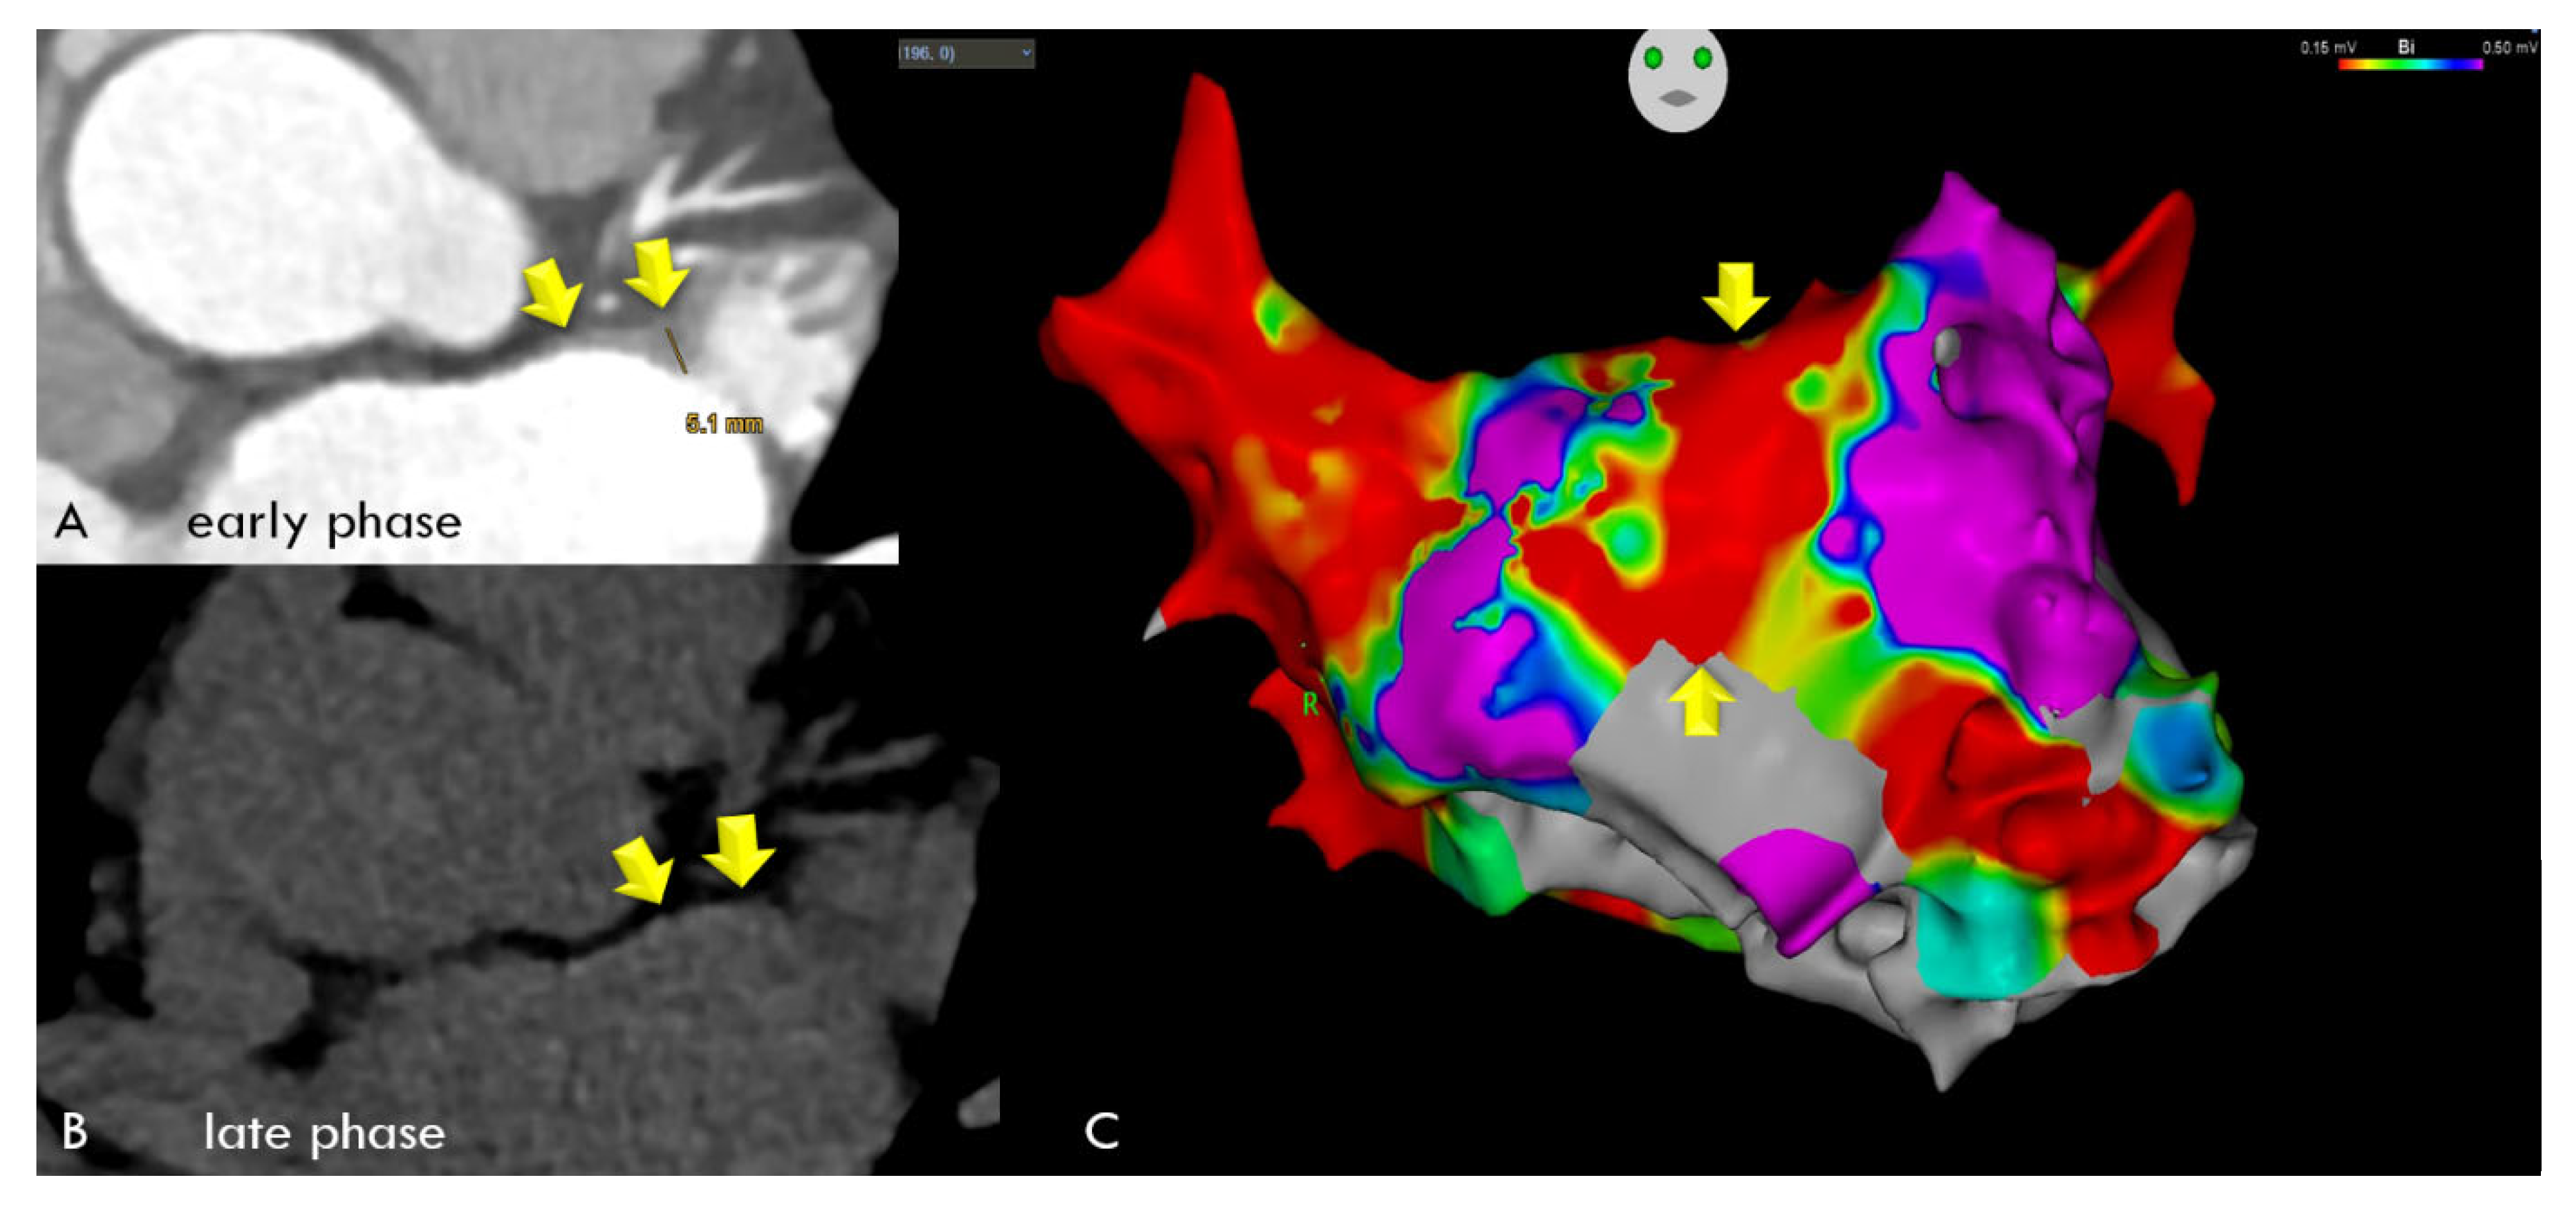

Late Enhancement Computed Tomography for Left Atrial Fibrosis Imaging: A Pilot “Proof-of-Concept” Study

2.2. Computed Tomography (CT)

2.3. Electroanatomical Mapping and Left Atrial Catheter Ablation